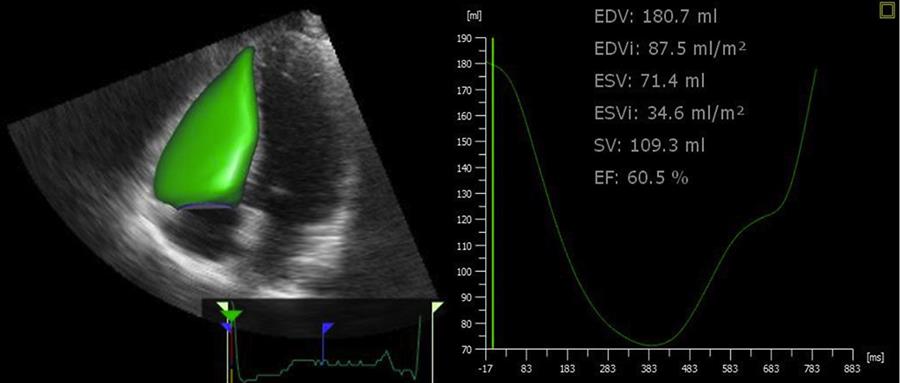

Rendering dinamico 3D della superficie endocardica del ventricolo destro (a sinistra) è ottenuto insieme alla curva volume-tempo, da cui si ottengono i parametri di dimensione e funzione del ventricolo stesso (a destra). (1)

L'ecocardiografia tridimensionale consente misurazioni accurate e riproducibili delle dimensioni e della funzione del ventricolo destro. Tuttavia, l'implementazione diffusa dell'eco 3D nella pratica clinica di routine è ancora limitata, perché i software esistenti richiedono tempi relativamente lunghi e competenze molto elevate negli operatori.

In un terzo di pazienti non selezionati, il nuovo algoritmo ha fornito una misurazione del volume del ventricolo destro e della frazione di eiezione accurata e completamente riproducibile. Nei restanti pazienti, le misurazioni sono state ragionevolmente accurate, con un'eccellente riproducibilità. Questo approccio rappresenta quindi una soluzione promettente per l quantificazione tridimensionale rapida delle dimensioni e della funzione del ventricolo destro.